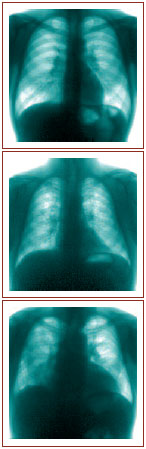

Клиническая картина определяется вовлеченными в патологический процесс органами и степенью их анатомических и функциональных нарушений. Особенное практическое значение приобретает диагностика поражений легких из-за наиболее частого вовлечения в процесс. Выделяют четыре стадии поражения легких:

0 – нормальная рентгеновская картина груди;

I – двустороннее, чаще асимметричное, увеличение региональных лимфатических узлов;

II – двусторонняя, связанная с корнями легких, диссеминация (милиарная, очаговая) и/или инфильтрация преимущественно средних и нижних отделов легких;

III – распространенный пневмосклероз (фиброз) с крупными сливными фокусными образованиями.

Саркоидоз легких II, III стадий может осложниться обтурацией бронхов, эмфиземой легких, дыхательной недостаточностью, легочным сердцем.